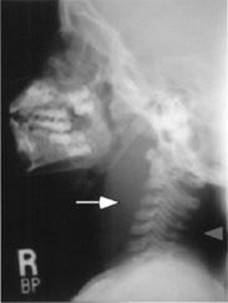

Steeple sign—narrowing of tracheal air column just below the vocal cords (see Figure 12-1).

FIGURE 12-1. Radiograph demonstrating steeple sign of croup.

Note narrowing of airway (arrow). (Courtesy of Dr. Gregory J. Schears.)